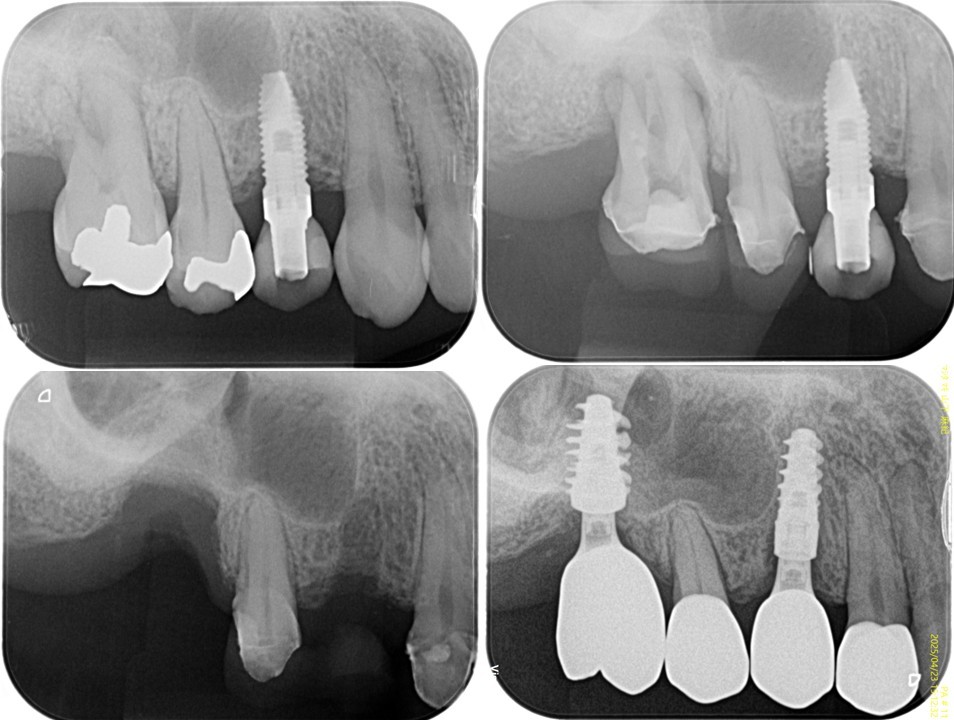

(図25)治療経過

上4番のインプラント再埋入待ちの補綴装置装着状態

(図26)術後レントゲン像

左上1番以外は天然歯は全て有髄歯の状態で保存できている